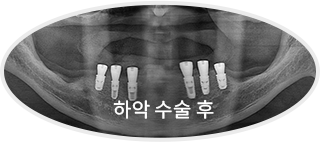

소수의 임플란트로

전체 치아를 지지하는 구조를 만들고,

상태에 따라 보철을 진행합니다.

치료 후 사진